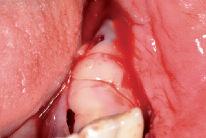

Nach crestaler Schnittführung, vestibulärer und lingualer Abpräparation, vestibulärer Entlastung und Freipräparation des N men talis erfolgte die Periostschlitzung vestibulär

5 | Konditionierung des zu augmentierenden Bereiches mit einem Knochenschaber und kortikalen Bohrungen; Anprobe des passgenauen Gitters